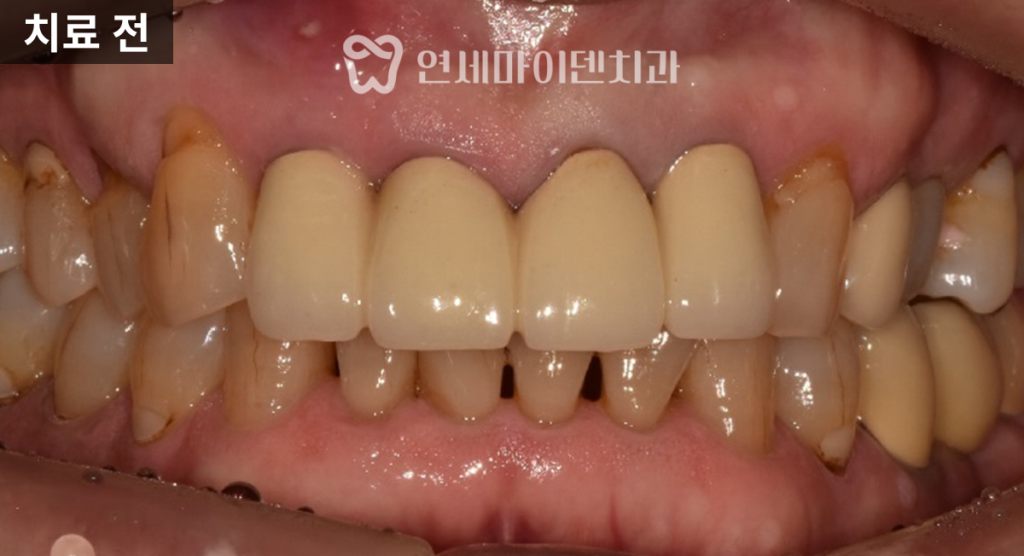

이번 케이스는

앞니가 반복적으로 붓고

고름이 생기며

발치 가능성까지 거론되던 상황이었습니다.전치부 앞니 네 개가

스플린트 크라운, 즉 여러 치아가

하나로 묶인 보철 형태로 제작되어 있었고,

이로 인해 염증 부위를

명확히 구분하기 어려운 상태였습니다.

스플린트 크라운은

단기적으로 흔들림을 줄이는 장점은 있지만,

치실 사용이 어렵고

각 치아를 개별적으로 평가하기 힘들어

염증을 늦게 발견하는 단점이 있습니다.이런 경우 문제가 상당히 진행된 뒤에야